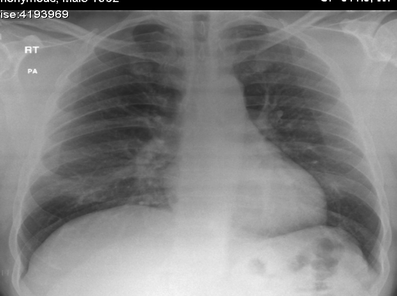

A 40-year-old man developed a swelling to his left side of his face during the course of a root canal treatment. He was undergoing some dental restoration of his left upper second molar. During the cavity preparation, the dentist noticed some swelling over the left parotid area that slowly started to spread to the left cheek and lower eyelid. The root canal treatment was stopped, and the patient was referred to our emergency department as an allergic reaction/anaphylactic reaction by his dentist in an ambulance. Examination revealed a swollen left half of his face (Fig. 1) with crepitus on palpation. There was no trismus. There was no increase in the size of the swelling during his stay in the department. There was no dysphagia. The vital signs were normal, and he was apyrexial. The cardiovascular and respiratory system examination was normal. The sudden onset of head and neck swelling after a dental procedure made us draw up a list of differential diagnoses that included haematoma, cellulitis, allergic reaction, angioedema and subcutaneous emphysema. However, we managed to exclude the others one by one on clinical examination, haematological, biochemical and radiological investigation. Haematoma was unlikely as there was no active bleeding during the procedure or after the procedure. There was no tenderness on palpation, no visible haematoma on intra- or extra-oral examination, no history of clotting abnormalities, and his clotting studies were normal. Cellulitis was unlikely as there were no local signs of inflammation such as warmth, redness, tenderness or raised temperature. The white cell count and the C-reactive protein were normal as well. The swelling was localised to the left half of the face and neck with no other rash or swelling elsewhere. The patient was not known to be allergic to any substances and had undergone previous root canal procedures under the same dentist. This ruled out an allergic reaction. Furthermore, intraoral examination did not reveal any swelling to the tongue or the uvula or lips, etc. There was no family history of allergy or angioedema. He was not on any medications that could have caused angioedema. Furthermore, angioedema swelling does not produce palpable crepitus. This ruled out an angioedema. There was palpable crepitus felt over the swelling on clinical examination. Given that an air turbine dentist drill was used, a diagnosis of subcutaneous cervico-facial emphysema was made. The subcutaneous emphysema was confirmed on facial x-rays (Fig. 2). A chest x-ray was also performed to rule out the presence of a pneumomediastinum (Fig. 3). The patient was admitted to our Clinical Observation Unit and was provided with high-flow supplemental oxygen via a reservoir bag. He was also treated with antibiotics (Co-Amoxiclav 625 mg three times a day for 7 days). No antihistamines, adrenaline or corticosteroids were used in his management. The patient made an uneventful recovery, his facial swelling subsided, and he was discharged home around 14 h after his initial presentation to the Emergency Department.